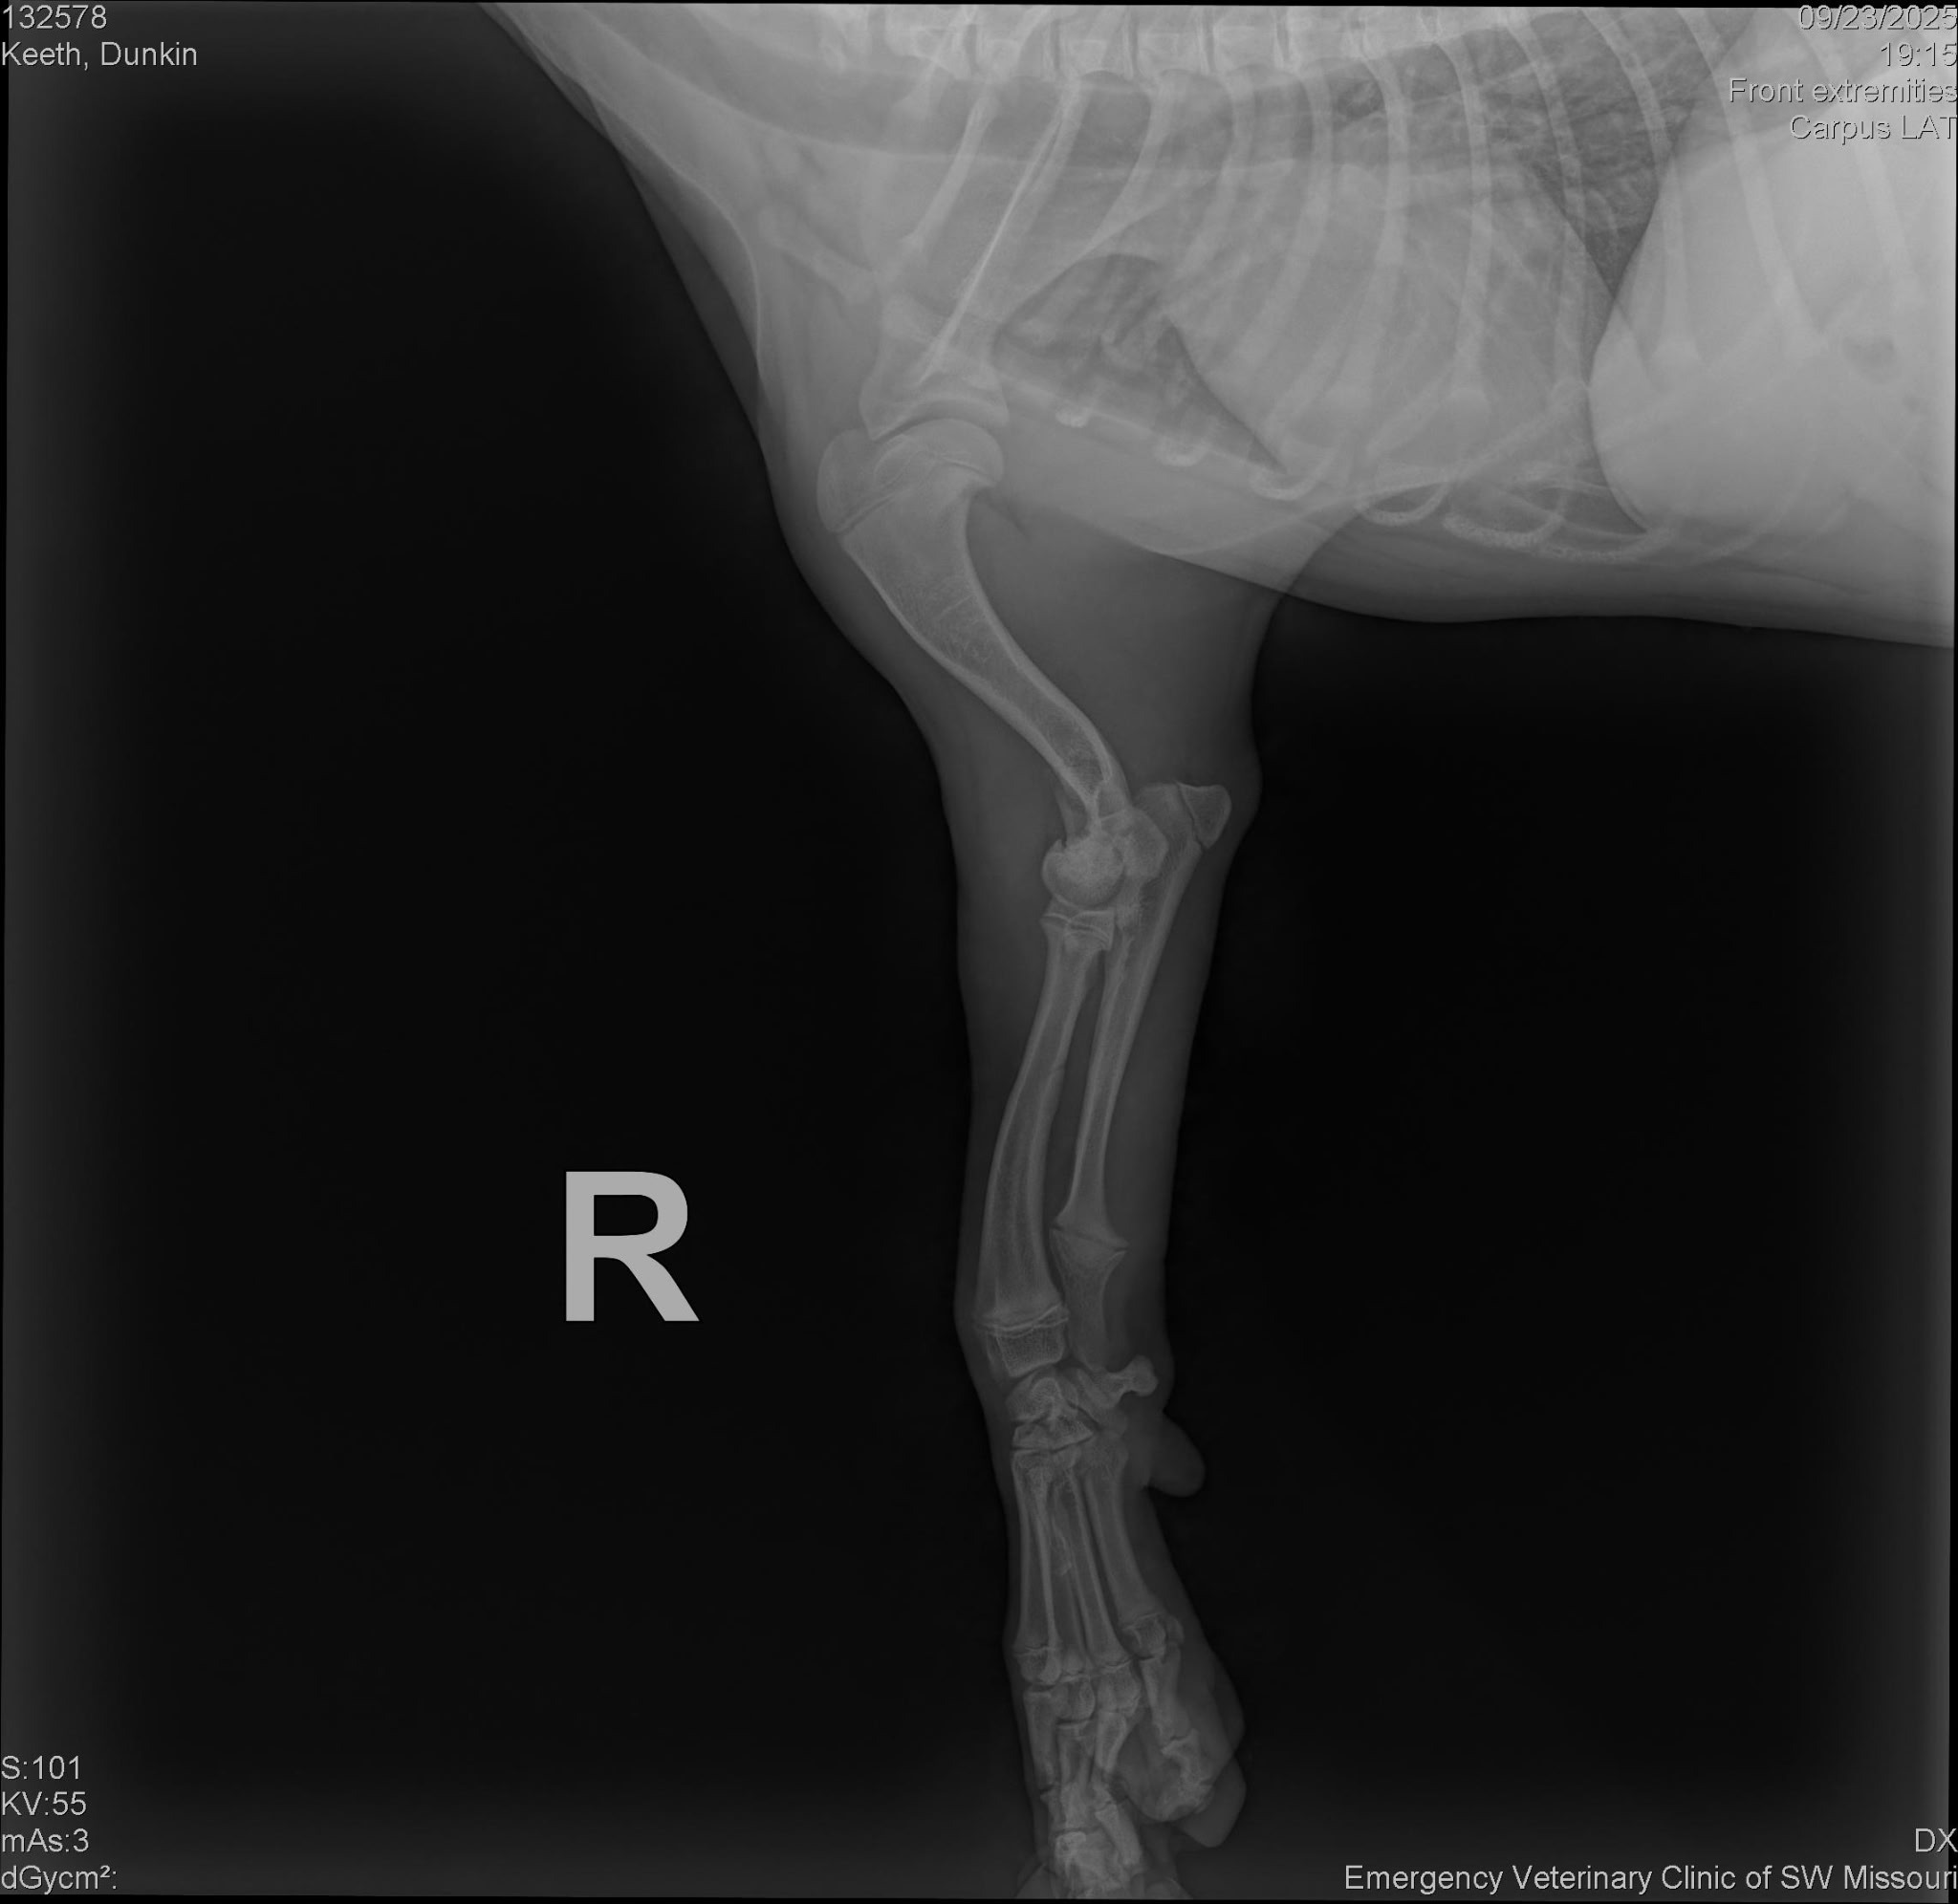

A few days ago, Dunkin hurt his leg, and the vet gave us heartbreaking news: he has fractures in both the lateral and medial condyles of his leg. To fix it, he needs surgery that costs $6,000. If we can’t raise the money, the only other option is amputation for about $1,000.